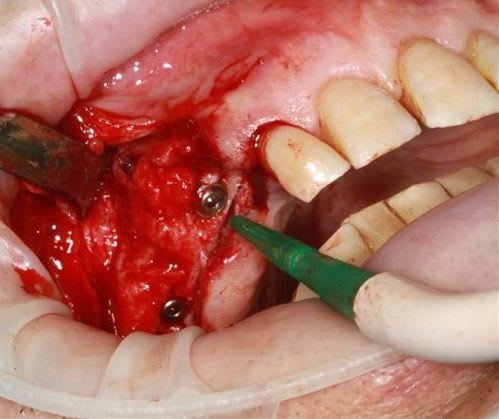

Puis 40120 en 15 avec léger SL, à l'ostéotome, et 40120 en 17.